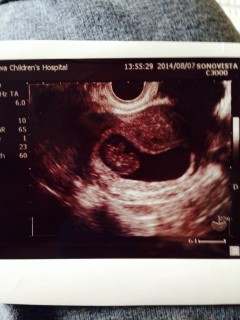

一週間前より頭や手足がはっきりしてきました! 撮影中なかなか動かないな、と先生と画面 ガン見してたら急に頭がピコピコ上下して、 うごうごしてました!可愛いかったです。

基礎体温・排卵検査薬では8w4dの計算だったのですが、本日予定日確定して、9w2dみたいです! 順調な様で母子手帳の手続きも出来て、まだ夢みたいでしたが少し実感が出てきました^ ^ 次は2週間後待ちきれません(。-_-。)